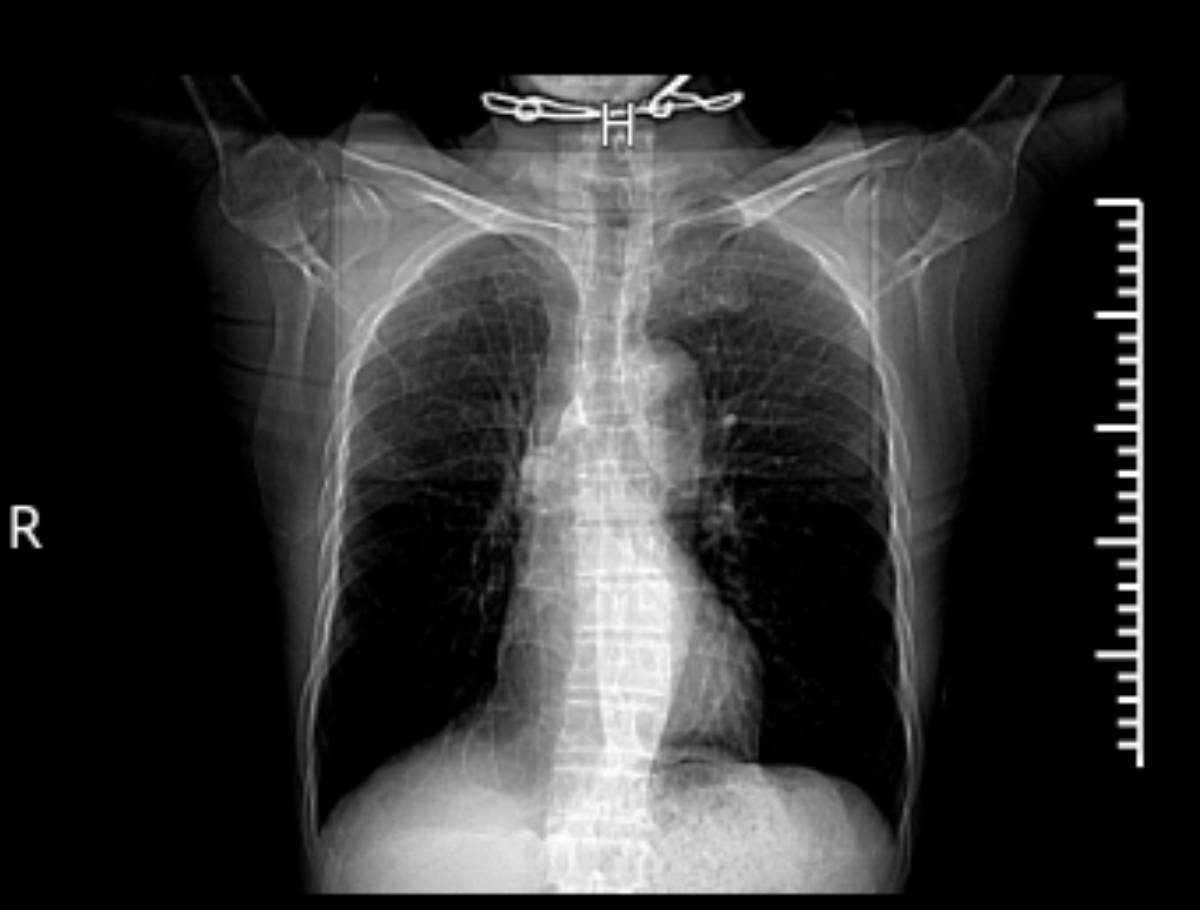

天有不测风云,人有旦夕祸福,谁知病情又起波澜,去年6月因疫情需要,入院治疗必须做胸部CT检查。当CT报告出来后,医生告知我肺部有结节可能需手术切除,让我转院去专科医院治疗。心急火燎的我一出院就赶往上海市胸科医院挂上了专家号,专家看了我的病史后,立即安排了入院手术前的各项检查,等检查结束后马上手术。从发现到手术只有一周时间,2021年6月22日幸运的我成功切除了病灶,手术很成功。十天后病理确认为:右肺上叶浸润性恶性腺癌。主刀医生说,幸亏早发现,及时得到了处理,不然后果不堪设想。所以我真的很感谢为我治疗的中医医院主治医生、胸科医院的白衣天使们,是他们对病人高度负责的精神,才让我有这么好的运气。